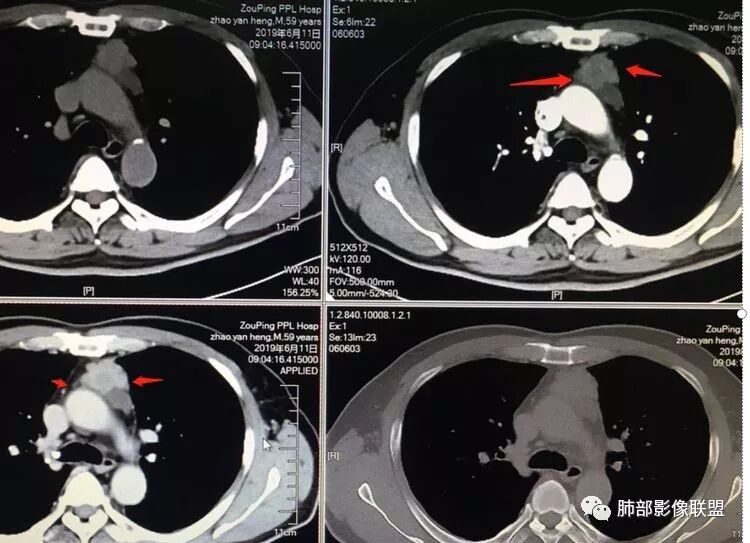

因为原病灶没看到,现在原有位置有一大病灶,如果是新发的,原有病灶会推移一边,但是没看到,倾向于原病灶增大

根据强化,高的70HU,低的没测,考虑囊实性

实性部分明显强

偏一侧

上面来的血供,病灶深分叶

附近心包似乎也不干净

有淋巴结

从前后变化,病灶的形态、强化、附近的淋巴结、心包改变,支持恶性

前纵隔肿物,形态不规则,位置居中,肿块内可见侵蚀的血管影及大片状坏死灶,心包及纵隔胸膜受累,定性为恶性,有心包及纵隔胸膜受累,坏死边界不清,年龄偏大,可除外胸腺瘤A一AB型及淋巴瘤,综和考虑胸腺鳞癌或B3型胸腺瘤

胸腺癌—非角化鳞状细胞癌